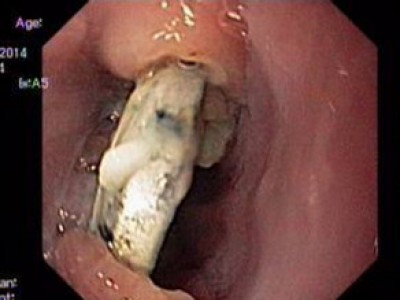

Foreign body ingestion

Lesion: The boy 2-year old had a 2cm diameter bouton battery at the upper one-third of esophagus with ulcers, about 2cm from upper esophageal sphincter